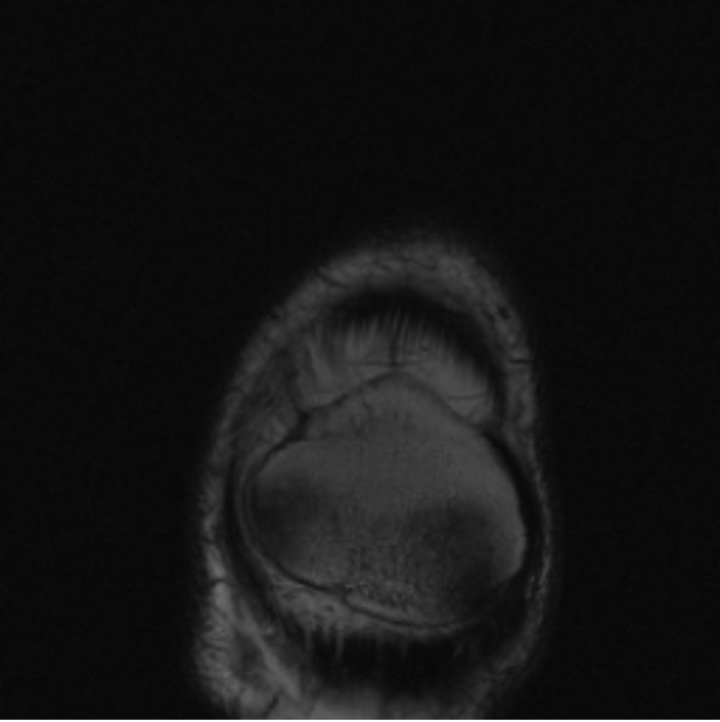

5.3 Out-of-Domain Generalisation

One way to test the generalization capability of the trained X-Diffusion is to test it on a completely different domain from an MRI dataset not seen during training. We report the single-slice results on NYU fastMRI [37, 82], a knee MRI dataset, using the X-Diffusion trained on the BRATS brain MRIs. The results are shown in Figure 9 and Table 2. It shows how successfully X-Diffusion is able to generate knee MRIs from a single image, despite not seeing knees at all in training. To qualitatively assess how realistic our generated 3D volumes were (produced from a single slice), we gave 20 generated examples alongside their real MRI counterparts to an expert orthopaedic surgeon. He was then asked to identify the real example from a given pair. The surgeon identified with certainty only 10 real knee MRIs out of 17, while could not decide on the remaining 3 of the 20 MRI pairs. This further validates the generated out-of-domain MRIs.